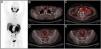

Radiotherapy is a treatment with curative intent, both in patients with primary diagnosis of prostate cancer (PCa) and in patients presenting with biochemical recurrence after radical prostatectomy (RP). Moreover, the use of stereotactic body radiotherapy as a metastasis directed therapy in patients with oligometastatic PCa has significantly increased in the recent years. Conventional imaging techniques, including transrectal ultrasound, computed tomography (CT), morphologic magnetic resonance and bone scintigraphy have traditionally played a minor role in all those clinical scenarios due to its low diagnostic accuracy. The recent development of the positron emission tomography (PET) radiotracer 68Ga-PSMA binding to the prostate specific membrane antigen (PSMA), a transmembrane glycoprotein overexpressed in PCa cells, has shown promising results. Detection rates for PCa lesions are higher than CT and higher than the best technique available, the PET/CT with choline. Its superiority has been demonstrated even at very low PSA levels (<1 ng/ml). This increase in diagnostic accuracy represents a potential impact on patient management, especially in radiotherapy. Even if this imaging technique is already available for routine clinical practice in some European countries, in Spain, unfortunately, there is very limited access. In this review, we analyze the main studies that investigate the usefulness of 68Ga-PSMA PET/CT in patients with PCa and its potential impact on radiotherapy treatments. In addition, we compared the 68Ga-PSMA PET/CT, with the multiparametric magnetic resonance imaging and the PET/CT with choline, in the different clinical scenarios.